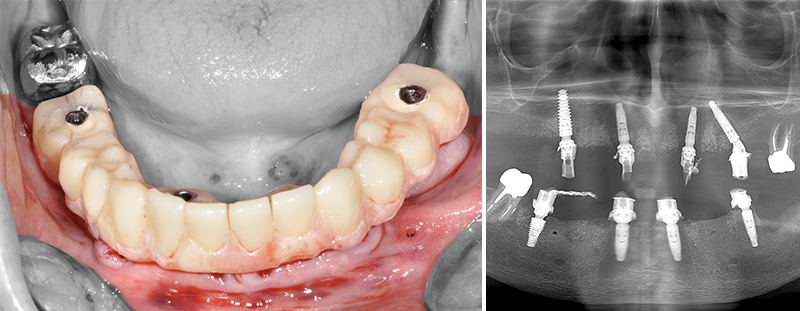

Fig. 49 : pour montrer la précision des ajustages, les guides sont imprimés par le laboratoire Giraud tandis que la restauration provisoire est conçue et usinés par Createch.

Fig. 50 : comme précédemment, le guide de forage des emplacements des clavettes s’appuyant sur les structures initiales est utilisé en premier.

Fig. 51 : les dents sont extraites sans lambeau par fractionnement puis le guide de résection osseuse est inséré et claveté dans les emplacements précédemment forés.

Fig. 52 : le guide de forage et de mise en place des implants est empilé sur le guide de résection osseuse.

Fig. 53 : vissage des piliers prothétiques dans les implants.

Fig. 54 : transvissage des gaines temporaires sur les piliers.

Les piliers prothétiques sont immédiatement vissés dans les implants sans déposer le guide de résection osseuse ; des gaines temporaires en titane sont transvissées sur les piliers et la restauration transitoire empilée sur le guide de résection, pour être solidarisée en bouche avec une colle composite. La finition très simple est réalisée au fauteuil et le patient quitte le cabinet dès la fin de la chirurgie avec sa restauration provisoire.

Fig. 55 et 56 : restauration provisoire terminée.